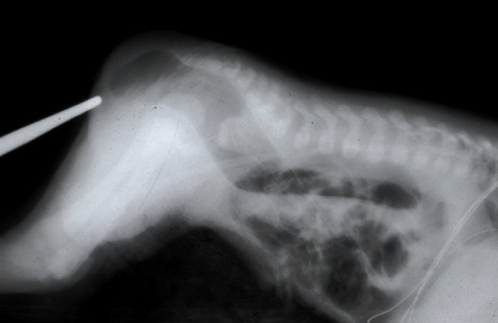

diagnosis: xray (cross table)

cross table X-ray:

Anal: X-Ray